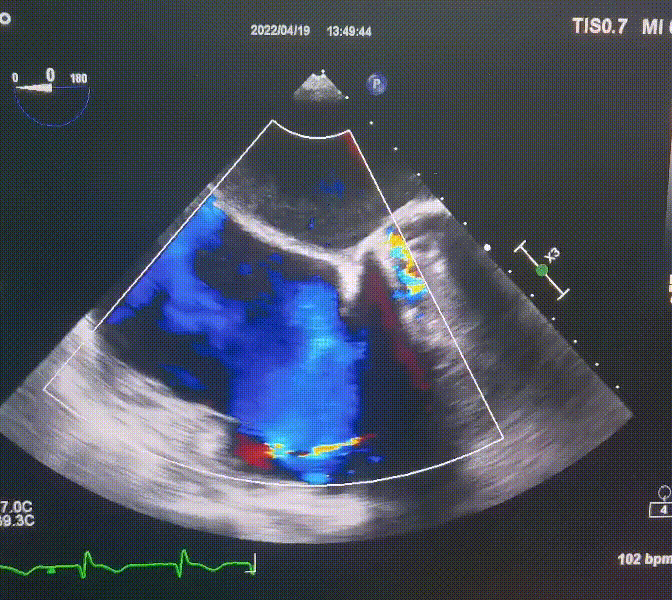

3.三尖瓣環(huán)巨大擴(kuò)張,收縮期瓣葉對(duì)合不攏,收縮期三尖瓣房側(cè)見(jiàn)大量反流信號(hào),反流面積15-20cm²,TRVmax:240cm/s,跨瓣壓差:23 mmHg。

圖1.術(shù)前超聲